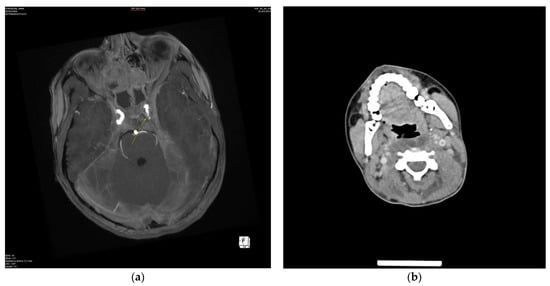

2.2. Case Two—Pansinusitis, Bilateral Otomastoiditis, and Parapharyngeal Abscess Complicated by Acute Mediastinitis, Thrombophlebitis, and Vein Thrombosis

2.2.2. Initial Assessment and Hematological and Radiological Investigations